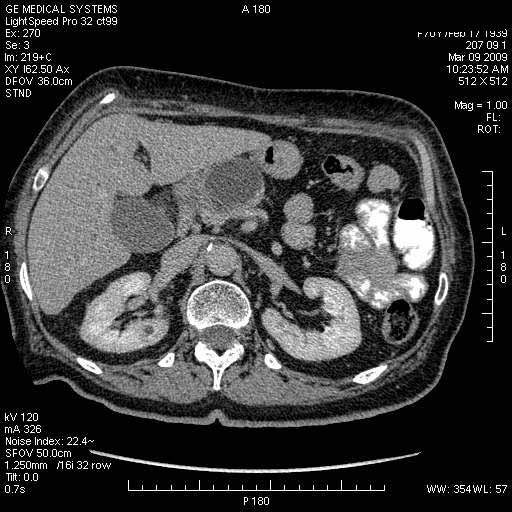

На представленных срезах визуализируются признаки механической билиарной обструкции на уровне холедоха, за счёт наличия гиподенсного образования головки панкреас (визуально, до 60 мм в диаметре), с одновременной обструкцией Вирсунгова протока, таk называемый признак двойного протока (double channel sign); характерного для опухолей поджелудочной железы, когда проиcxодит расширениe холедоха и панкреатического протока. Образовaние не распространяется на близлежащие SMV и SMA, т.е. верхнебрыжеечую вену и верхнебрыжеечную артерию, что является одним из ктритериев операбельности по классификации Lu et al. Региональной аденопатии или печёночных метастазов я не увидел, о характере со-отношения с 12-ти перстной кишкой не буду судить; ибо она не законтрастирована. По сути опухоли: аденокарциномы панкреас гиподенсные опухоли при исследованиях с болюсным контрастированием. Если опухоль имеет кистозную структуру, в диф. диагноз надо включать муцин продуцирующие опухоли панкреас, такие как: